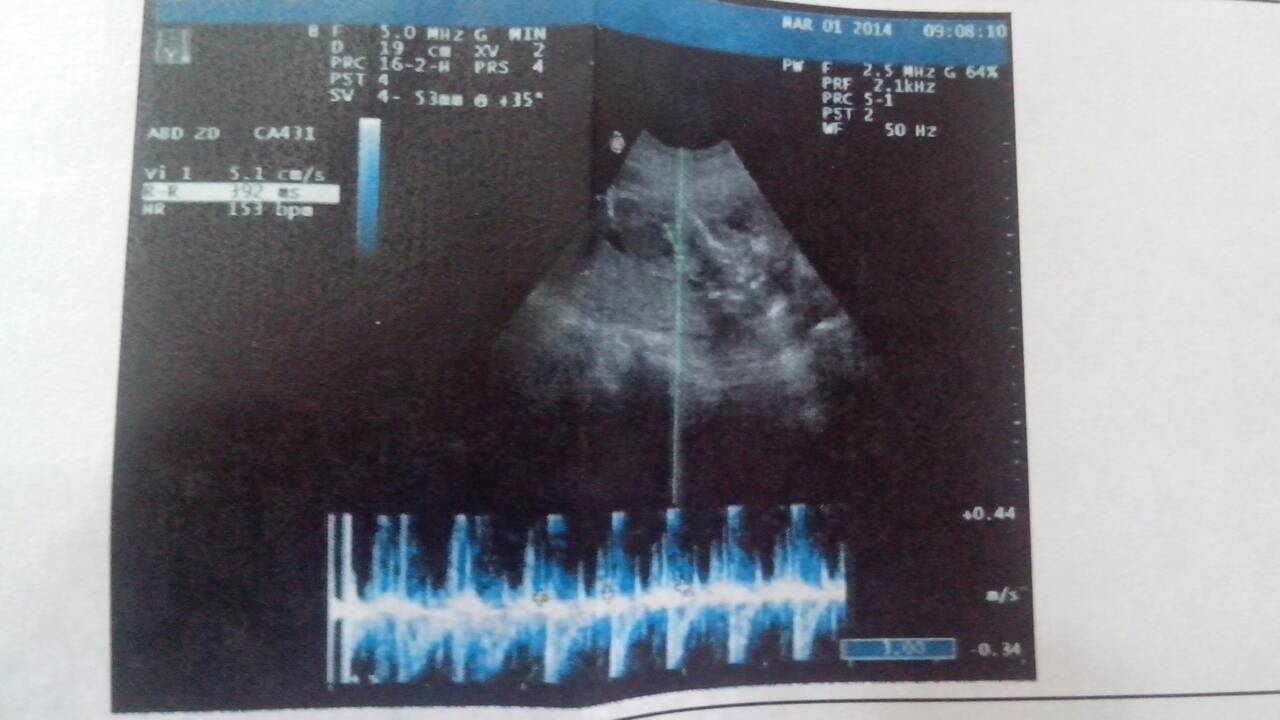

超声所见:双顶径:46.0mm 胎心率:153次/分 胎盘位于子宫体后壁,I级;胎盘厚度:29.3 超声所见:双顶径:46.0mm 胎心率:153次/分 胎盘位于子宫体后壁,I级;胎盘厚度:29.3mm 羊水厚度:47.0mm 请问能不能知道是男孩还是女孩?只是好奇,健康就好!谢谢 点击展开 匿名用户 2014-03-01 10:29 为您推荐: 其他回答 病情分析: 你好,就你所述的情况,这是常规胚胎数据的结果。 指导意见: 这些结果不是胎儿性别参数指标,所以,报告不可能暗示你胎儿性别的,祝你健康。 匿名用户 2014-03-01 10:53 相关问题 超声所见:双顶径;39mm 股骨长度;19mm,胎心率;153次、分 胎盘位置;前壁,胎盘成熟度0 双顶径88mm,头位,股骨长69mm,胎心率145次/分,胎盘位于子宫前壁,厚35mm,胎盘成羊 双顶径88mm,头位,股骨长69mm,胎心率145次/分,胎盘位于子宫前壁,厚35mm,胎盘成羊